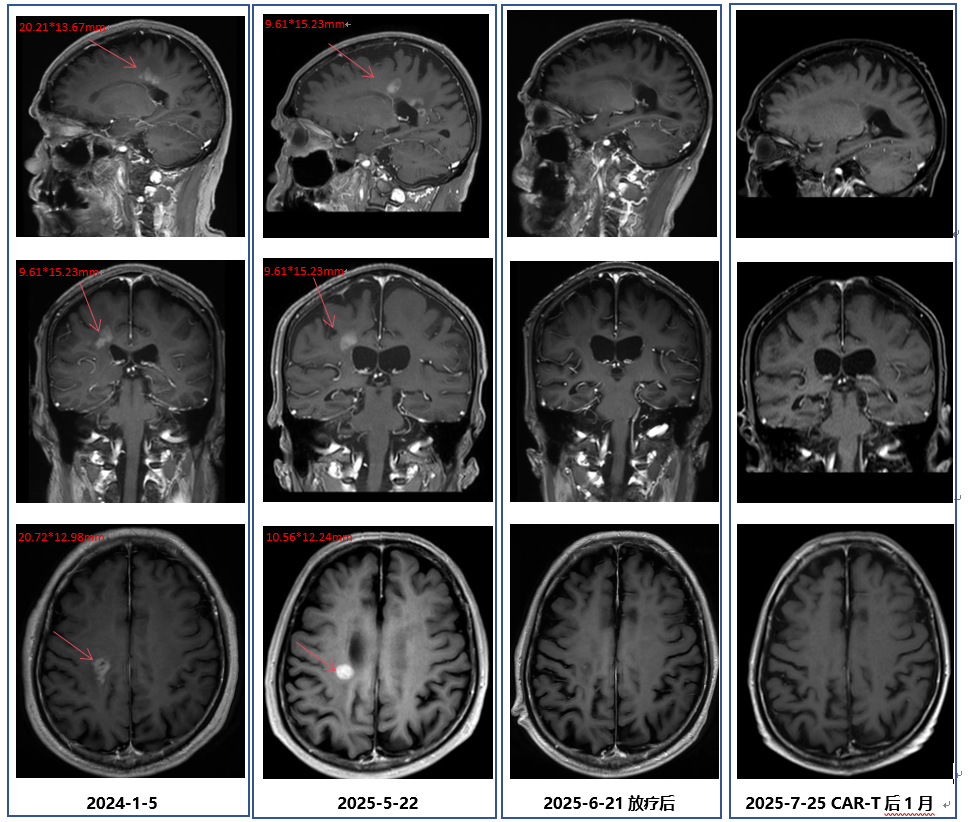

· 2025年5月,外院进行的头颅MRI检查结果显示,该患者的肿瘤再次进展。基于患者目前的疾病情况,中心医生先对其行全脑放疗,使用BTK抑制剂口服治疗,并且同步准备CAR-T细胞培养。此外,该患者还接受了氟达拉滨联合环磷酰胺方案进行预处理治疗,并于6月26日成功回输CD19 CAR-T细胞。在放疗后,患者的头颅MRI提示颅内病灶较前明显减少、减小。而CAR-T细胞治疗后50天复查PET-CT显示,患者的颅内肿瘤病灶已完全消失,达到完全代谢缓解(CMR)

图4.png图2. 患者 PET-CT结果(CAR-T细胞治疗后50天)